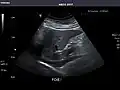

Renal ultrasonography

Ultrasound scan of a kidney (right side)

Ultrasonography of the kidneys is essential in the diagnosis and management of kidney-related diseases. The kidneys are easily examined, and most pathological changes in the kidneys are distinguishable with ultrasound.[7]